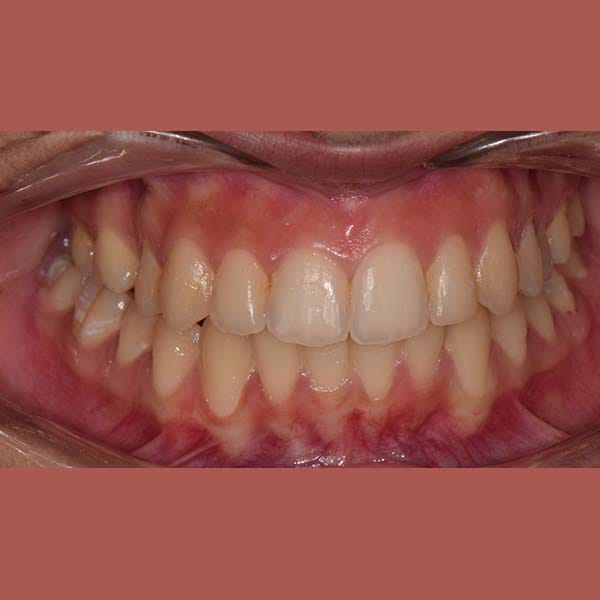

AFTER

At the end of the treatment, we were able to see a clear expansion in her upper jaw, her teeth were aligned beautifully, and the gap resulting from the absence of the molar was closed orthodontically.